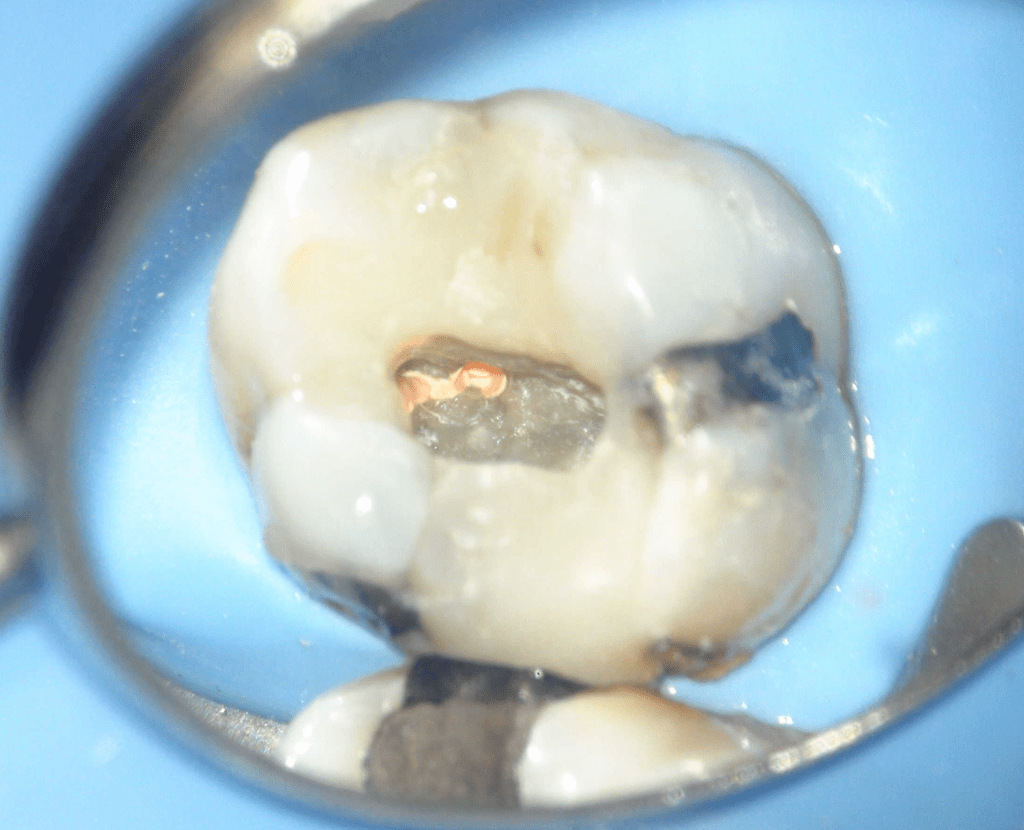

Fisura, remoción amalgama para explorar